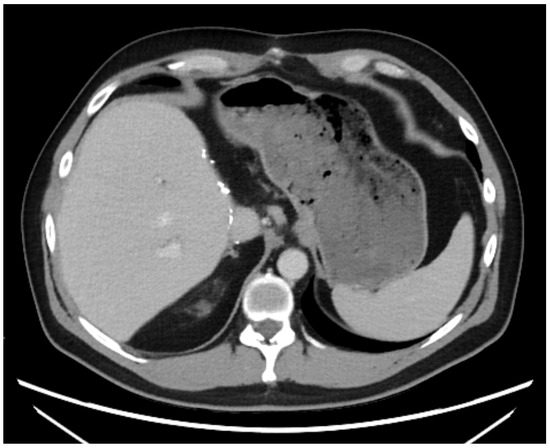

A 43-year-old man went because of persistent fatigue to the general practitioner. The diagnostic showed a large tumor within the central liver (see Figure 1a), which was biopsy-proven as a moderate-differentiated intrahepatic cholangiocarcinoma. An extrahepatic tumor spread could be ruled out (applying an FDG-PET-CT scan, see Figure 2a). Due to the invasion of the hepatic veins, which precluded a primary resection, chemotherapy with cisplatin / gemcitabine was initiated. The tumor showed a partial response (see Figure 1b). We decided to perform surgical exploration with the intent of an ex situ liver resection. Due to an invasion in liver segment VII, even an extended left trisegmentectomy was not possible. We performed an SIRT of both liver lobes resulting in a further, even metabolic (Standardized Uptake Value, SUVmean of the tumor in the initial PET scan: 7.3; SUVmean after treatment: 3.0), response of the tumor (see Figure 2a,b). The CA19-9 levels were always below the reference value. Twenty-two months after the initial diagnosis, the patient could be transplanted with a right living donor lobe from a friend. Histopathologic examination showed an intrahepatic cholangiocarcinoma with a maximum diameter of 6.3 cm. The tumor stage was ypT3, N0, L0, V0, Pn0, R0. Currently, 17 months after the LDLT, the patient is recurrence-free and in good clinical health (see Figure 3). The most recent CA19-9 level is 21.3 U/mL (reference value < 27.0 U/mL).

Figure 3. State 15 months after LDLT.